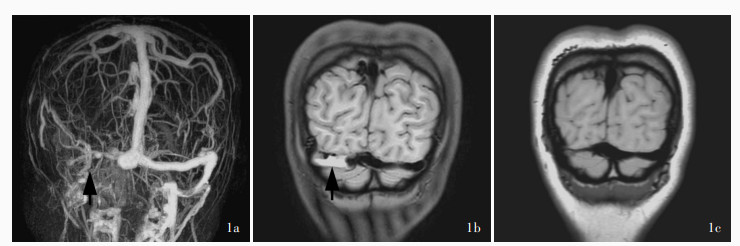

Yang X, Wu F, Liu Y, Duan J, Fisher M, Ji X, Meng R, Zhang H, Fan Z, Yang Q. Diagnostic performance of MR black ‐ blood thrombus imaging for cerebral venous thrombosis in real ‐ world clinical practice. Eur Radiol, 2022, 32: 2041- 2049.